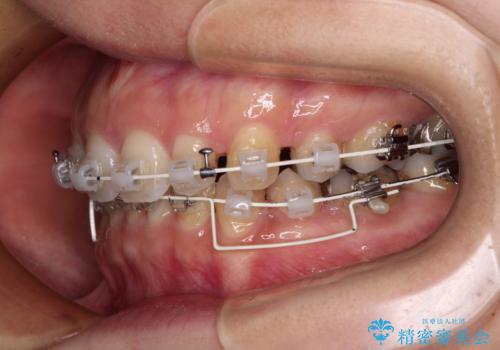

- 審美装置

上下左右第一小臼歯4本を抜歯し、ワイヤー装置にて口元を引っ込めるよう矯正治療を行うこととしました。

奥歯が前方に傾斜していることで深く咬みこむ(ディープバイト)状態であったので、なかなか抜歯したスペースが閉じず、様々な方法でディープバイトを改善しながら治療を進めていくこととなりました。